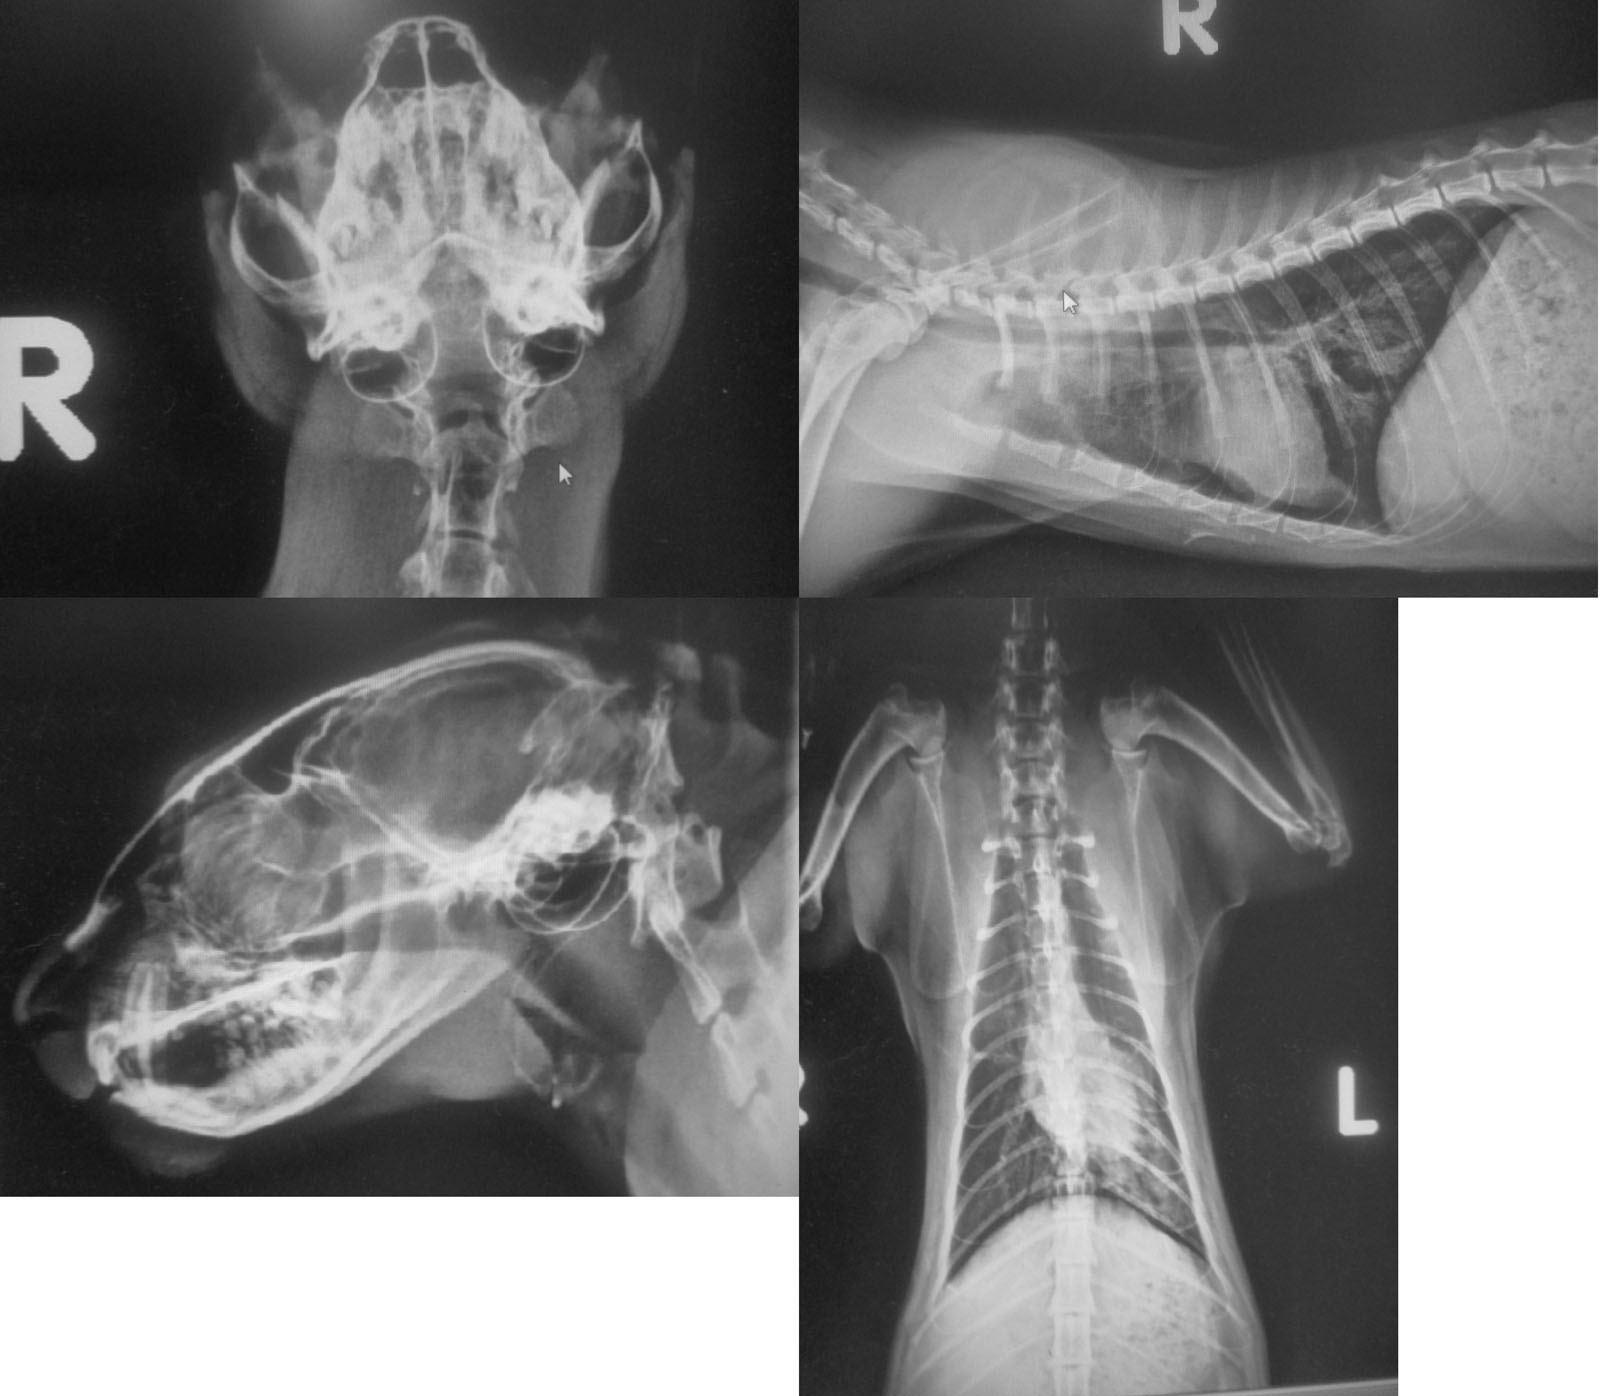

主題: 深夜遭撞擊下顎聯合骨斷裂及氣胸/肺受創..等的黑浪 申請者姓名: 又旅(阿莫) 花色: 申請日期: 2019-01-13 00:08:31 申請者部落格: 申請者臉書網址: https://www.facebook.com/musso.lin.1 所在縣市/合作醫院: 高雄市/樂生動物醫院 治療費用: 30750元 需求人數: 65人 已結案 (2024-05-31 18:37:36) 報名人員: Ivy(已付款)、詩詩(已付款)、Pin-Chen Lu(已付款)、酷比(已付款)、賣悶啦 x2(已付款)、Kitty Chen x2(已付款)、游凌蕙(已付款)、Ingham Kao(已付款)、mibicat(已付款)、Yu(已付款)、Bao x2、Yu x2(已付款)、Sysley Claudio Marchisio(已付款)、蘇小嵐 x2(已付款)、Zhiyun(已付款)、圈圈與花貓(已付款)、Neo(已付款)、vivian(已付款)、陳若凡(已付款)、Xero Knight(已付款)、Joyce914(已付款)、Win Chih Chen(已付款)、陳丁源 x5(已付款)、Trina Liu x2(已付款)、宸瑜(已付款)、Ivy(已付款)、Momo Yu x2(已付款)、賴小虎 x2(已付款)、賴小虎 x2(已付款)、catlover x3(已付款)、Ellery x2(已付款)、斑比(已付款)、熊哥(已付款)、Shan Chou x10(已付款)、Mickey Han(已付款)、Annie(已付款)、Yi-Ling Yao x2(已付款)、廖小強、Ada Chen(已付款)、Angel Lin(已付款)、Gina Pan(已付款)、賴小虎(已付款)、 候補人員: 動物病情說明: 貓咪狀況:黑浪疑似遭撞擊,頭部及胸腔及肝臟皆有受創,頭部唇部外傷,下顎骨聯合斷裂,顳顎關節半脫位,胸腔有氣胸,左肺受創,血檢除白血球過高外,肝指數也過高顯示肝臟也有受創,目前已初步鎮定清理外傷並安置食道胃管,下顎聯合斷裂也已復位固定,同時待置ICU氧氣房,目前生命跡象穩定但仍有3~7天的危險期。 動物近況說明: 初期已將重創的下顎做聯合骨固定+顳顎關節半脫位復位手術與清創,並投以肝藥、嗎啡止痛(前5日)、以食道胃管灌食,持續觀察危險期中。